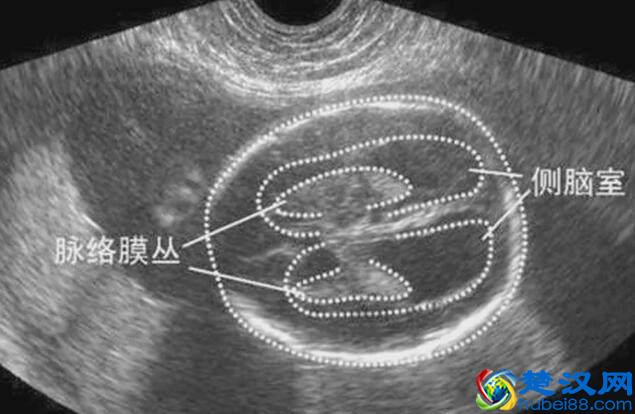

第一类,颅内的结构

颅内的结构,有时候大家可能会看到,侧脑室增宽,或者是侧脑室未见明显增宽。这个侧脑室,实际上是胎儿颅内的一个正常的结构,那么向我们经常会听到的脑积水,它带来的一个结果就是侧脑室会增宽,增宽到不同的程度,它发生异常的风险也不一样。

颅内的结构,我们还需要描述的包括小脑以及后颅窝的宽度,这个实际上都是评价胎儿颅内发育情况的,